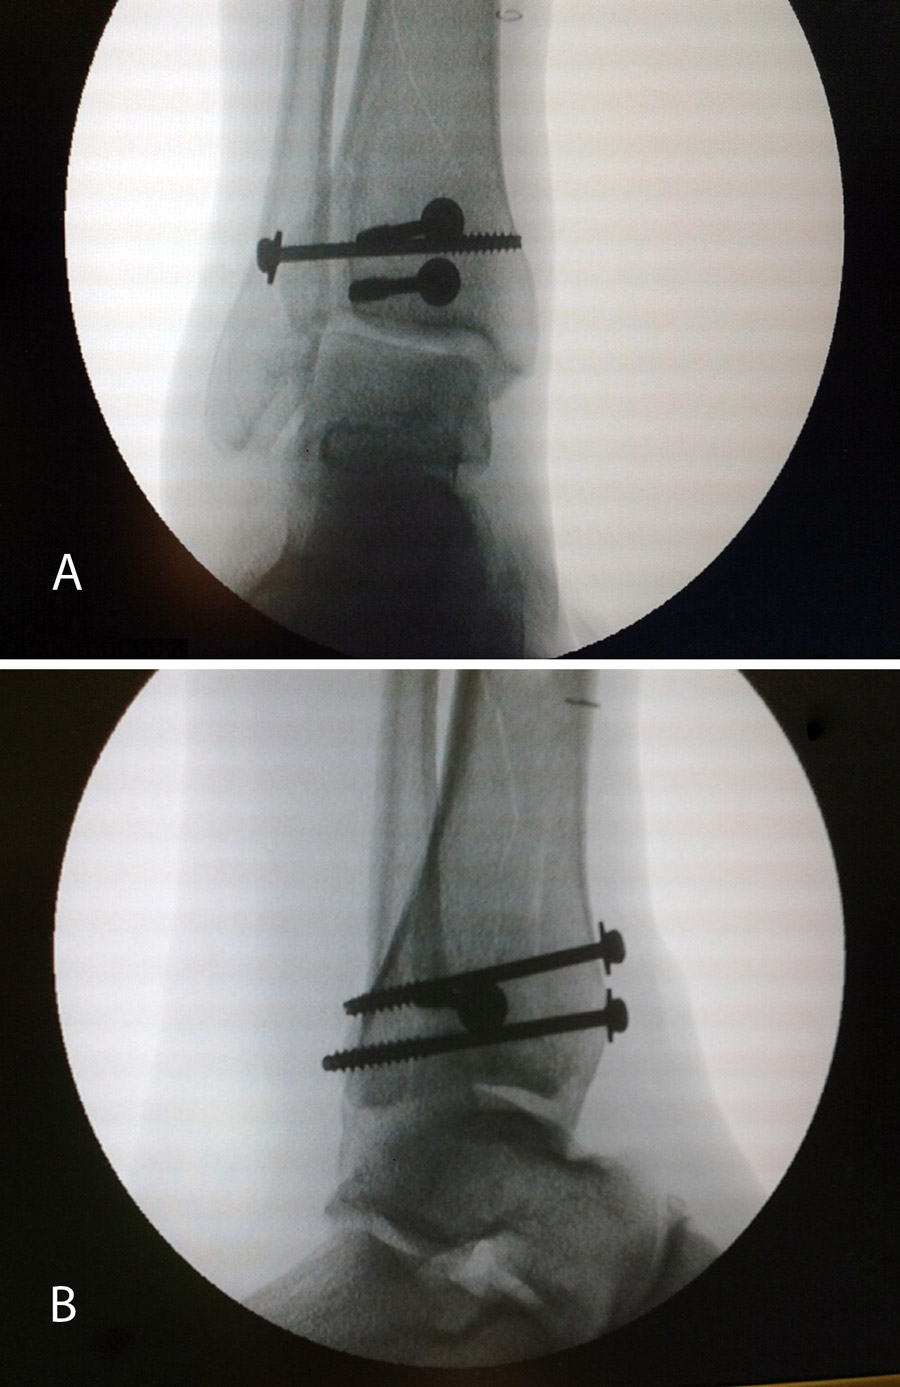

Figura 10. Colocación de los tornillos. Control radioscópico.

Figura 11. Control radiológico anteroposterior y lateral.